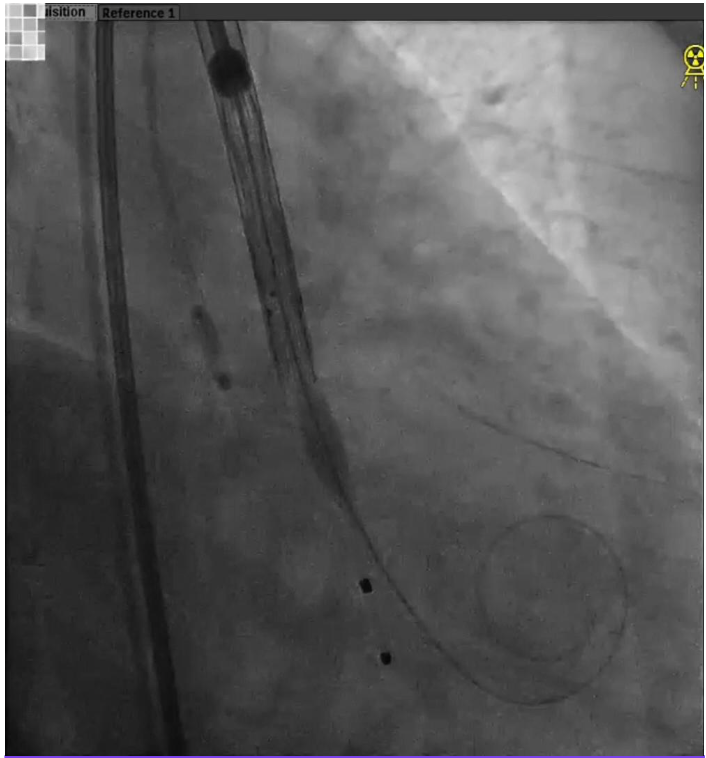

脑保护输送系统置入;

导丝跨瓣;

猪尾导管交换预塑形导丝;

TaurusEliteAV23第一次释放,预释放;

初始定位;

近左右重合位,瓣下1mm释放,释放过程中瓣膜下滑瓣膜展开至工作位;

左冠切线位评估,瓣架底边对齐,左冠显影良好,大弯侧深度约8mm,同轴性较差,瓣膜几无压缩,决定回收;

TaurusEliteAV23第二次定位、释放;

零位释放,瓣膜位置过高,回收并进行第三次释放。第三次释放后,多体位根部造影评估,瓣架底边对齐,左冠显影良好,瓣膜明显位移,同轴性较差,瓣膜压缩,决定第三次回收;

第四次定位和释放,右窦中心位,瓣上2mm释放;

根部造影评估,瓣架底边对齐,左冠显影良好,同轴性一般,瓣膜压缩,锚定良好,瓣下深度4-5mm;

瓣膜脱钩,完成释放,最终造影显示瓣膜形态佳,未见明显反流;

回撤脑保护装置,完成手术。